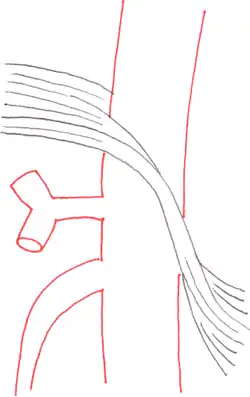

The median arcuate ligament is a ligament formed at the base of the diaphragm where the left and right diaphragmatic crura join near the 12th thoracic vertebra. This fibrous arch forms the anterior aspect of the aortic hiatus, through which the aorta, thoracic duct, and azygos vein pass. The median arcuate ligament usually comes into contact with the aorta above the branch point of the celiac artery. However, in up to one quarter of normal individuals, the median arcuate ligament passes in front of the celiac artery, compressing the celiac artery and nearby structures such as the celiac ganglia.[2] In some of these individuals, this compression is pathologic. It leads to the median arcuate ligament syndrome.[2]

Further evaluation and confirmation can be obtained via angiography to investigate the anatomy of the celiac artery.[5] Historically, conventional angiography was used, although this has been largely replaced by less invasive techniques such as computed tomography (CT) and magnetic resonance (MR) angiography.[2][5] Because it provides better visualization of intra-abdominal structures, CT angiography is preferred to MR angiography in this setting.[5] The findings of focal narrowing of the proximal celiac artery with poststenotic dilatation, indentation on the superior aspect of the celiac artery, and a hook-shaped contour of the celiac artery support a diagnosis of MALS.[2] These imaging features are exaggerated on expiration, even in normal asymptomatic individuals without the syndrome.[2]

Proximal celiac artery stenosis with poststenotic dilatation can be seen in other conditions affecting the celiac artery.[2] The hook-shaped contour of the celiac artery is characteristic of the anatomy in MALS and helps distinguish it from other causes of celiac artery stenosis such as atherosclerosis.[2] This hooked contour is not entirely specific for MALS however, given that 10–24% of normal asymptomatic individuals have this anatomy.[2]